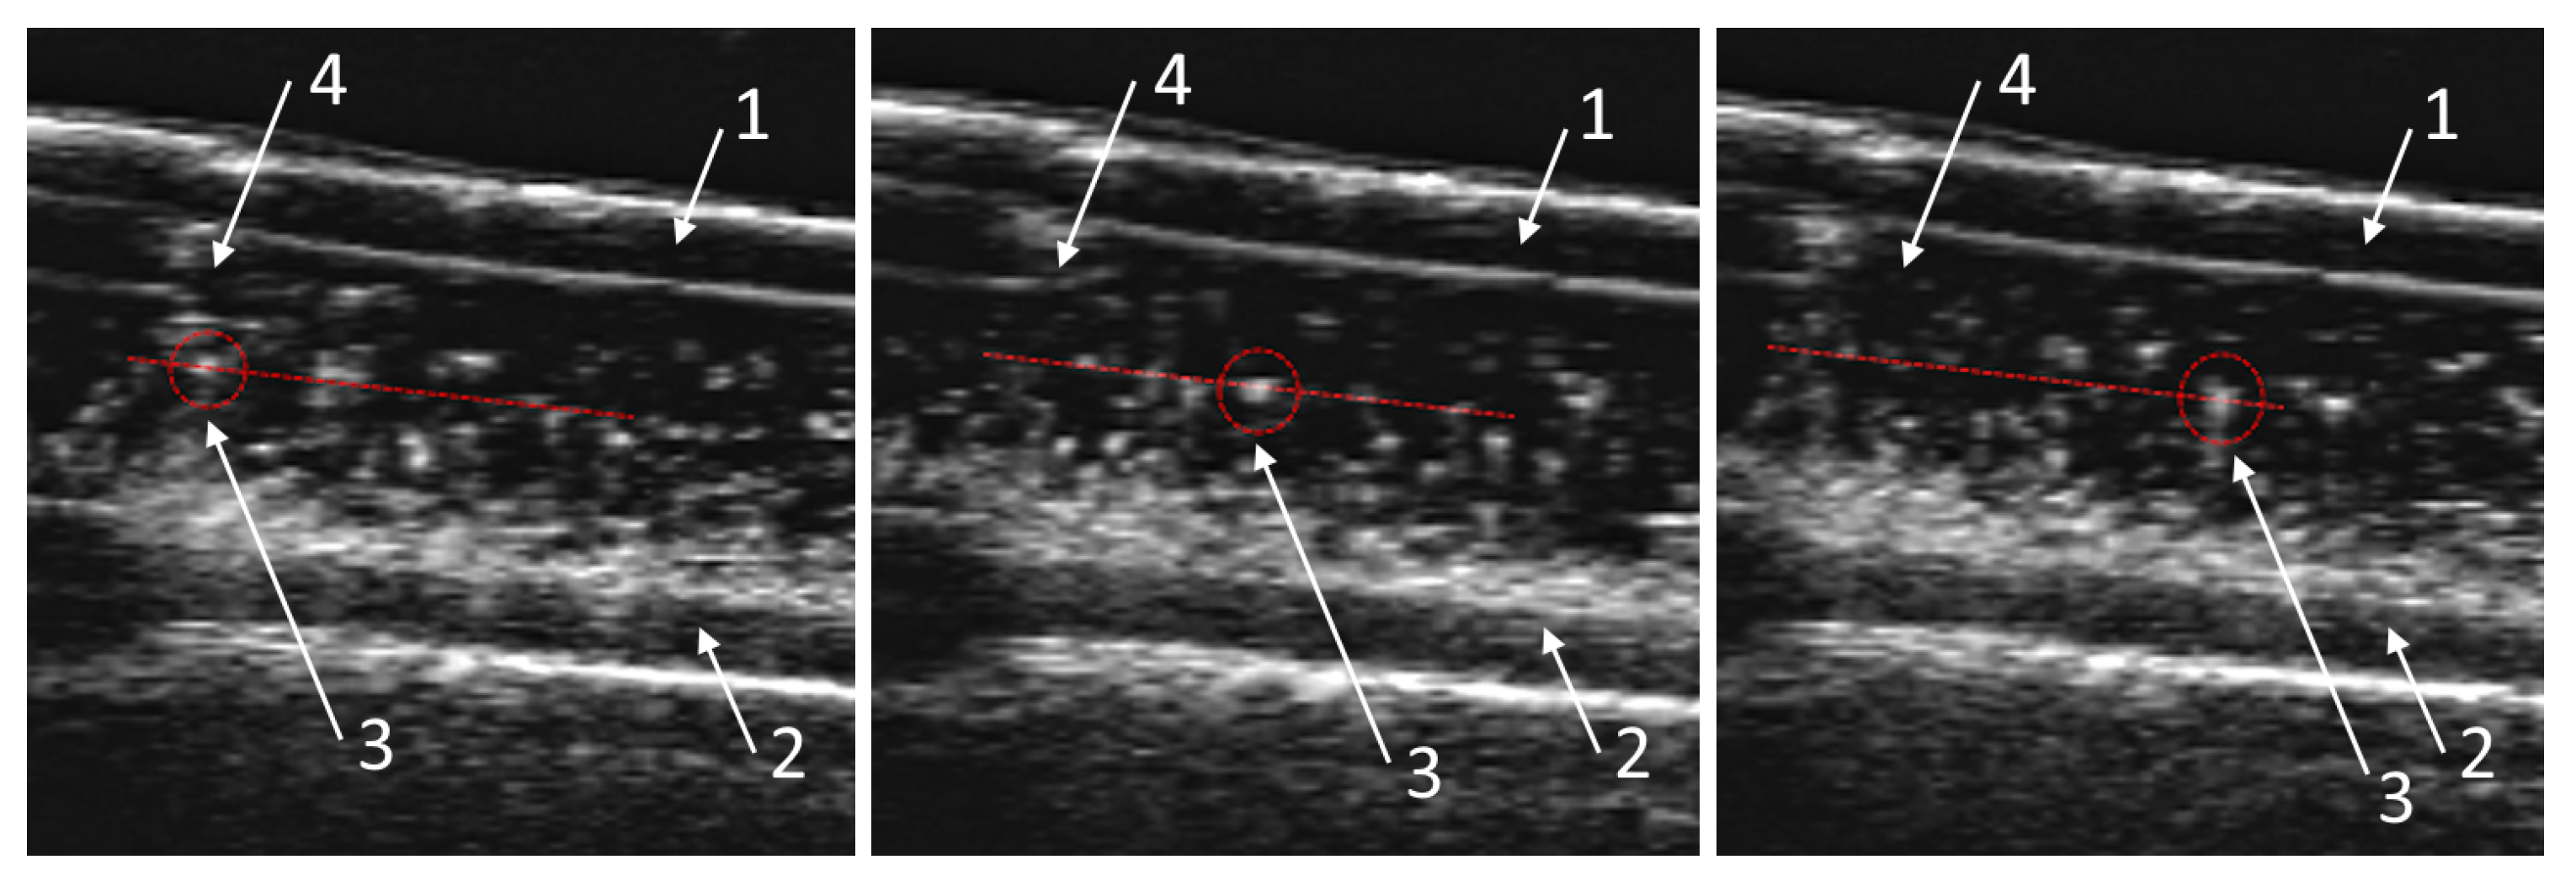

3.1. Obtaining the Vortex Zone by Echo-PV Tracking of Calcite Particles